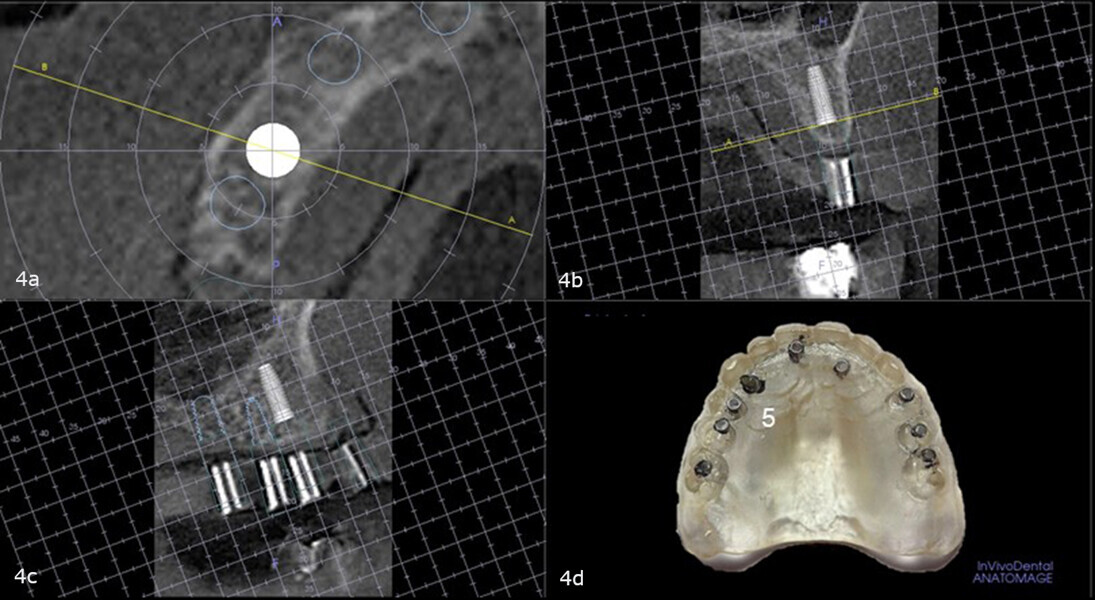

The maxillary right first premolar site was analysed for placement of a fixation screw to stabilise the full-arch surgical guide, and sufficient bone was found to be present to accommodate a 17 mm screw without contacting the maxillary sinus. No angular or linear correction would be needed (Figs. 4a-d).

Figs. 13a & b: Putty base with the corrected lower parts of the two-piece guide posts replacing the 2 mm straight guide posts for the planned sites for the implants and fixation screws inserted (a). Straight and uncorrected guide posts in the sites of the maxillary right second premolar, right first premolar, left first premolar and left second premolar. Offset guide posts in the sites of the right canine and right central incisor. Angle-corrected guide post in the site of the left lateral incisor (b).

An acrylic bur was used to make indentations in the putty base so that the rectangular bases of the guide posts were flush with the tissue. This completed the base for fabrication of the corrected surgical guide (Figs. 13a & b). The 3 mm upper removable part of each two-piece guide post was placed on to the lower part of each guide post to position the 3 mm-deep in guided sleeves (Fig. 14) that were to accommodate the 3 mm depth drill stops that would be utilised during the surgery (Fig. 15).